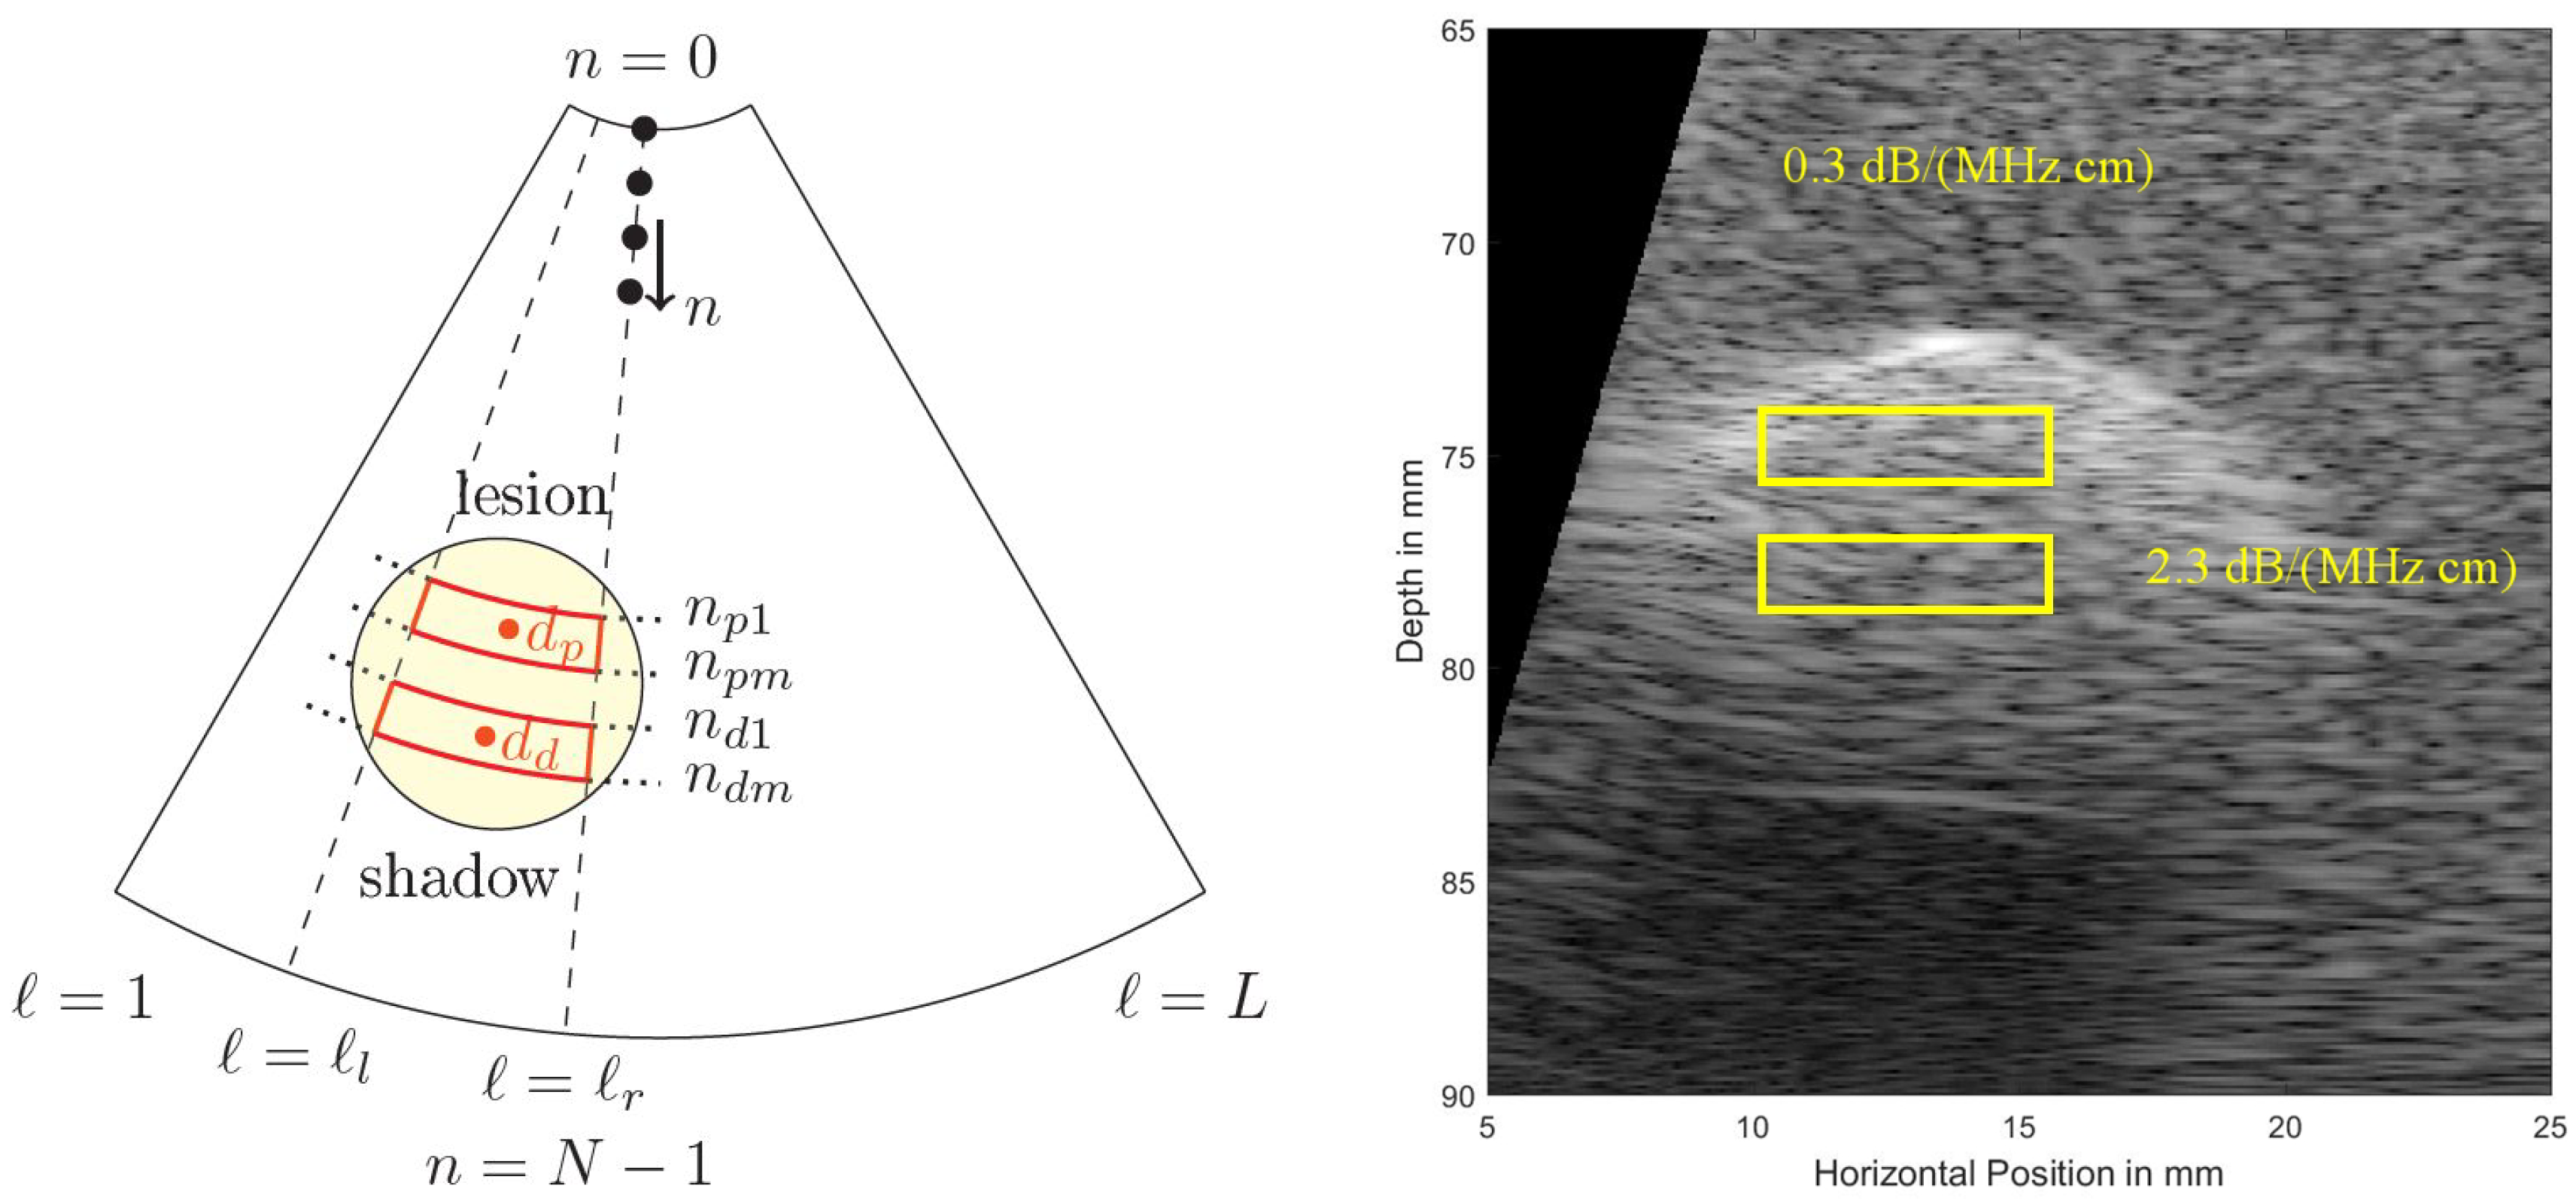

Figure 5 shows a cropped B-mode scan exhibiting the typical US speckles that are detrimental in the estimation process. Furthermore, the distal and proximal data windows over which both estimation algorithms operate are indicated. Note that here a phased array transducer was used with a steering angle of . The sketch in Figure 5, left, defines all indices used in both algorithms. Index is indicating the lateral sector scan line (typically going up to and beyond ), and index is indicating the depth dimension (typically being sampled at and beyond an MHz sampling rate). Given that the speed of sound, m/s, on the order of samples are acquired for each scan line for a typical cm depth range.

Figure 5.

(Left): To define locations and indices within a sector scan used in the estimation algorithms. At the top the US transducer is assumed operating as a phased array. (Right): Simulated US B-mode image, exhibiting typical US speckles and shadowing behind a strongly absorbing region (a simulated lesion). Distal (bottom, subscript (...)) and proximal (top, subscript (...)) windows are indicated.